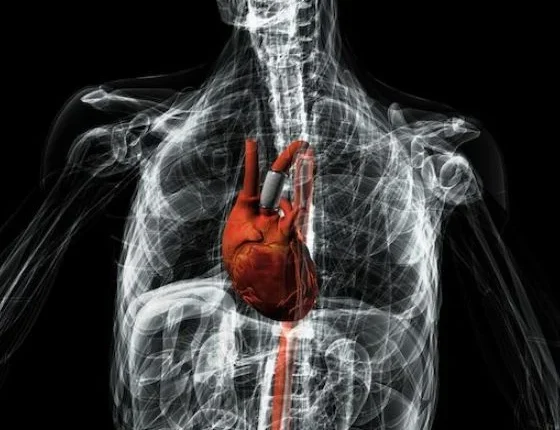

Nέα ηλεκτρονική αντλία για τη θεραπεία της καρδιακής ανεπάρκειας

Οι επιστήμονες έχουν δημιουργήσει μια νέα «έξυπνη ηλεκτρονική αντλία» που θεωρούν ότι θα φέρει «επανάσταση» στη θεραπεία των ασθενών που πάσχουν από χρόνια καρδιακή ανεπάρκεια.

Ερευνητές από το Πανεπιστήμιο του Νότιγχαμ λένε ότι το έξυπνο αορτικό μόσχευμα θα εμφυτεύεται στο σώμα και θα είναι εντελώς αυτόνομο, εξαλείφοντας την ανάγκη του ασθενή να εισαχθεί στο νοσοκομείο και να συνδεθεί με μηχανήματα.

Η συσκευή που θα λειτουργεί με μπαταρία θα εμφυτεύεται σε ένα τμήμα της αορτής που θα έχει προηγουμένως αφαιρεθεί, προκειμένου να βελτιωθεί η αποτελεσματικότητα της καρδιάς. Η αορτή είναι η μεγάλη αρτηρία που βρίσκεται στην αριστερή κοιλία της καρδιάς.

Ενας σωλήνας συνδέεται με τη συσκευή, που περιβάλλεται από ένα υλικό που διαστέλλεται όταν ασκείται τάση σ’ αυτό, με αποτέλεσμα να ενεργεί ως αντλία. Η συσκευή μπορεί στη συνέχεια να δημιουργήσει ένα μετρητή ροής του αίματος, χτυπώντας εκτός φάσης της καρδιάς του ασθενούς.

Αφού η καρδιά γεμίσει με αίμα, ο σωλήνας συστέλλεται, αυξάνοντας έτσι την πίεση στην καρδιά. Η καρδιά στη συνέχεια αντλεί το οξυγονωμένο αίμα σε όλο το σώμα. Αυτό αναγκάζει τον σωλήνα να διασταλεί, απελευθερώνοντας την πίεση και την αύξηση της ροής του αίματος.

Οι ερευνητές λένε ότι ελπίζουν πως θα έχουν τη συσκευή «κομμένη και ραμμένη» σε κάθε ασθενή, χρησιμοποιώντας τρισδιάστατες τεχνικές εκτύπωσης και τα δεδομένα από μαγνητικές τομογραφίες.

Ο Δρ Φίλιπ Breedon, της Σχολής Αρχιτεκτονικής, Σχεδιασμού και Δομημένου Περιβάλλοντος στο Πανεπιστήμιο Nottingham Trent αναφέρει ότι η τεχνολογία που χρησιμοποιείται σήμερα για να βοηθήσει τα άτομα με οξεία καρδιακή ανεπάρκεια μπορεί να χρησιμοποιηθεί μόνο για λίγες μέρες και περιλαμβάνει τη σύνδεση του ασθενή με μεγάλα εξωτερικά μηχανήματα που απαιτούνται για την κεντρική παροχή ενέργειας. Επομένως, η συγκεκριμένη συσκευή θα μπορούσε να κάνει τη διαφορά στη θεραπεία των ασθενών που πάσχουν από καρδιακή νόσο.

«Το πιο σημαντικό είναι πως τούς δίνεται η δυνατότητα να έχουν πλήρως εμφυτευμένη μια συσκευή που μπορεί να τούς σώσει τη ζωή, δίνοντάς τους κινητικότητα, αντί να τους αφήσει σε ένα κρεβάτι νοσοκομείου, συνδεδεμένους με σωστικά μέσα και με πολύ περιορισμένη κινητικότητα. Αυτή η συσκευή θα μπορούσε πραγματικά να είναι πρωτοποριακή και πιο αποτελεσματική από οποιαδήποτε άλλη θεραπεία που χρησιμοποιείται σήμερα σε όλο τον κόσμο», αναφέρει χαρακτηριστικά.

Η ερευνητική ομάδα σημειώνει πως τα περιστατικά καρδιακής ανεπάρκειας αυξάνονται σταθερά κάθε χρόνο, όπως αυξάνεται και το κόστος.

Το έξυπνο μόσχευμα αορτής είναι μια μοναδική πρωτοποριακή λύση σε ένα παγκόσμιο πρόβλημα υγείας και υπόσχεται να είναι φθηνότερη και καλύτερη από τις σημερινές συσκευές, λέει ο καθηγητής David Richens, σύμβουλος καρδιοχειρουργός στο Πανεπιστήμιο του Νότιγχαμ.

«Θα φέρει επανάσταση στον τρόπο που αντιμετωπίζονται οι άνθρωποι, ενώ οι τεχνολογίες που υποστηρίζουν το σχεδιασμό έχουν τη δυνατότητα να μετατρέψουν την θεραπεία και άλλων ασθενειών, όπως η αχαλασία του οισοφάγου. Σχέδια όπως αυτό, αποκαλύπτουν τις πραγματικές δυνατότητες των έξυπνων υλικών στον ιατρικό σχεδιασμό του προϊόντος. Η τεχνολογία θα μπορούσε να είναι η αρχή ενός νέου ξεκινήματος στον τρόπο που χρησιμοποιούμε τον εξοπλισμό, ώστε να βοηθήσει να σωθούν ανθρώπινες ζωές».